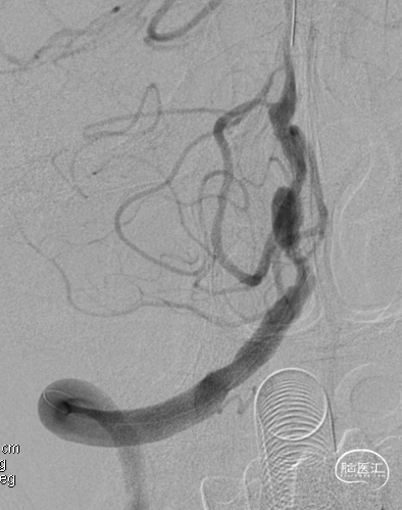

DSA示双侧椎动脉V4段狭窄,右侧为著且合并梭形动脉瘤。

术前DSA。